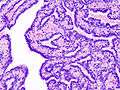

| Histopathology of intraductal papilloma of the breast by excisional biopsy. Immunostaining for p63 protein. | |

Histopathology of intraductal papilloma of the breast by excisional biopsy. Hematoxylin and eosin stain.- Histopathology of intraductal papilloma of the breast by excisional biopsy. Immunostaining for alpha-smooth muscle actin.